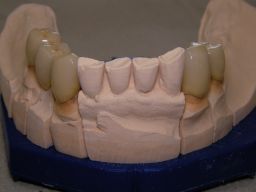

Die Bilder können alle angeklickt werden! Das Hauptproblem dieses Falles lag im Oberkiefer - die über die Jahrzehnte abgeknirschten, kurzen Zähne erschweren Kronen, die durch eine Prothese belastet werden können. Die gewählte Lösung besteht darin, die Zähne nur rundherum zu beschleifen, aber nicht mehr zu kürzen und die Prothese mit einem Druckknopfsystem an die Zähne anzukoppeln, das ein "Spiel" aufweist, so daß die Prothese nicht als Hebelarm auf die schwachen Restzähne wirken kann. Rechts die beschliffenen Zähne kurz vorm Zementieren der Kronen. |

Links das Bild zeigt das Metallgerüst, das später mit Keramik verblendet wurde. Um eine einfache Mundhygiene ebenso wie eine hohe zahntechnische Präzsion zu erreichen, wurden risikobehaftete Verblockungen minimiert. Rechts die Ästhetikeinprobe bei entspannter Oberlippe. |

Links Bilder des Oberkiefers, rechts des Unterkiefers. Die Arbeit wurde von dem Dentallabor "Heitmeyer Zahntechnik", Osnabrück, gefertigt. Dem Labor ist hier für die hervorragende Arbeit zu danken, dem Patienten für die Freigabe der Bilder! |